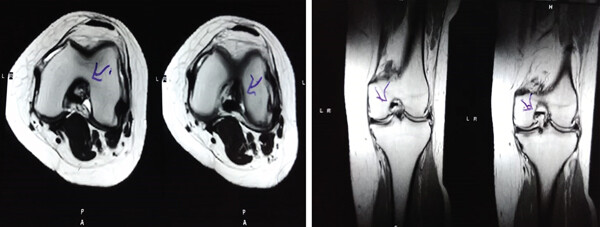

本研究的目的是比較半月板修復(fù)和滑膜間充質(zhì)干細胞 (MSC) 移植治療前后一年的退變皮瓣和內(nèi)側(cè)半月板 (MM) 放射狀撕裂的關(guān)節(jié)鏡發(fā)現(xiàn)情況。癥狀平均持續(xù)時間為24個月。

影像學(xué)檢查:4例MM皮瓣撕裂患者在治療前后交界區(qū)中央?yún)^(qū)域出現(xiàn)缺損,但其中2例患者該區(qū)域完全恢復(fù)穩(wěn)定光滑狀態(tài),另2例患者該區(qū)域部分恢復(fù)。治療前后交界區(qū)中央?yún)^(qū)域皮瓣撕裂的關(guān)節(jié)鏡評分為0.3±0.5,治療后為4.3±2.1,治療后評分顯著升高。2例患者原有放射狀MM撕裂在治療一年后愈合。

關(guān)節(jié)功能:治療后4周和52周的Lysholm評分顯著高于治療前。

安全性評估:未出現(xiàn)嚴(yán)重不良事件。

結(jié)論:間充質(zhì)干細胞移植后,隨訪24個月內(nèi),患者影像學(xué)和關(guān)節(jié)功能顯著改善,未發(fā)生嚴(yán)重不良事件。可以達到干細胞治療半月板損傷長期療效的目標(biāo)。